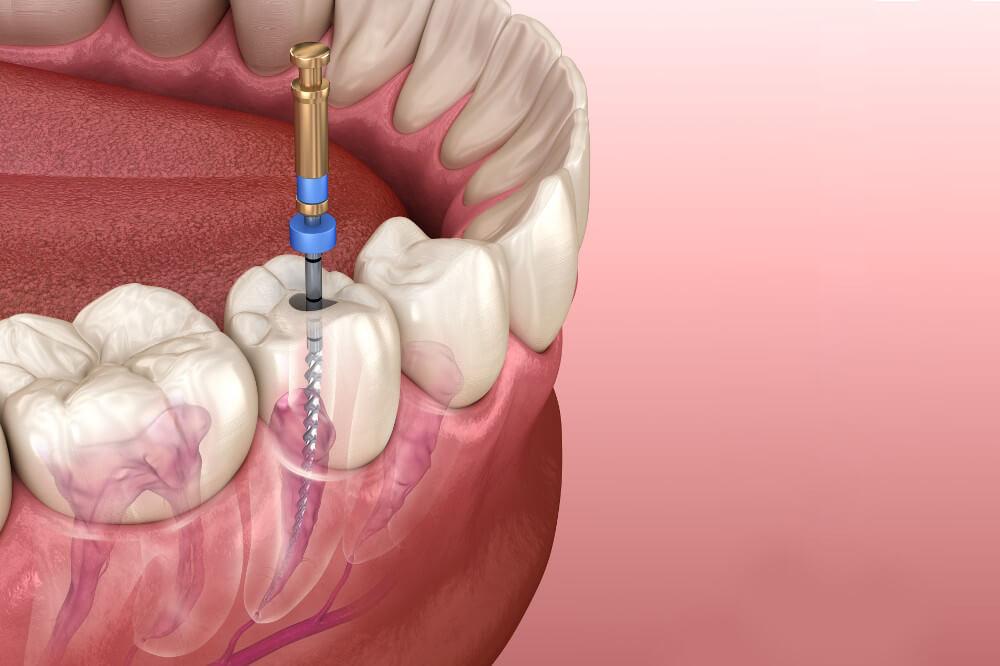

Реплантация зуба: Этапы и особенности операции